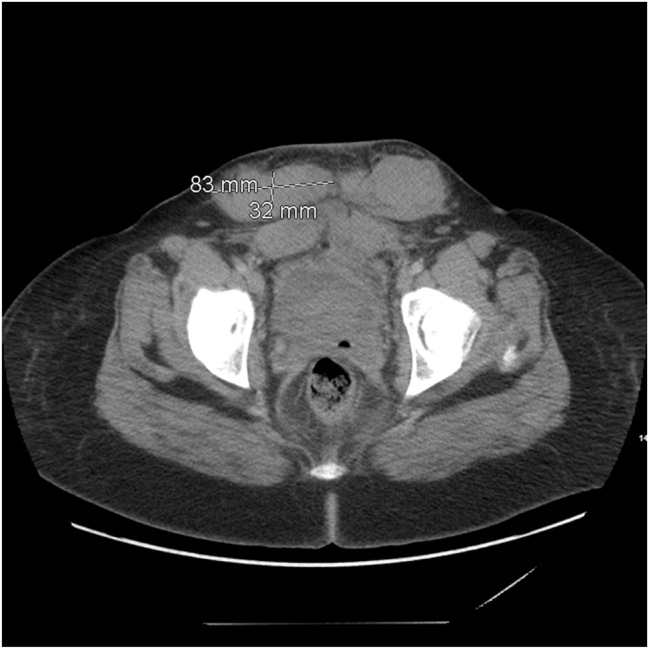

Case presentation: A 31-year-old woman was diagnosed with acquired factor VIII deficiency while undergoing induction of labor. Her labor and post operative course were complicated by epidural hematoma formation, prolonged postoperative surgical site bleeding, and subcutaneous hematoma. Management included blood products, human Factor VII, rituximab, and a steroid taper.